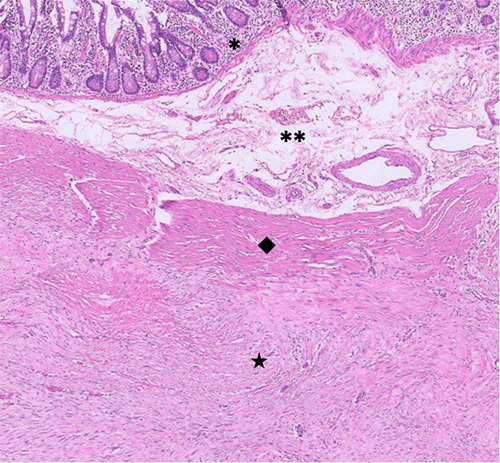

Histopathological examination revealed a subserosal fibromatosis extending into the small bowel wall without mucosal invasion (Figure 5A: H&E, x50). Higher magnification (Figure 5B: H&E, x400) showed spindle cell proliferation with somewhat ill-defined borders, comprised of uniform cells with plump ovoid nuclei and ample eosinophilic cytoplasm. The stroma was collagenous, focally edematous, and contained thin-walled small vessels scattered throughout the lesion. Additionally, some areas showed hyalinized, keloid-like changes. Resection margins were negative.

Figure 5. Hematoxylin and Eosin (H&E) Stains (50x and 400x, respectively). Published with Permission

A) Predominantly subserosal involvement characterized by an indistinct spindle cell proliferation, with localized extension into the muscularis propria (*mucosa; **submucosa; ◆muscularis propria; ★tumor)